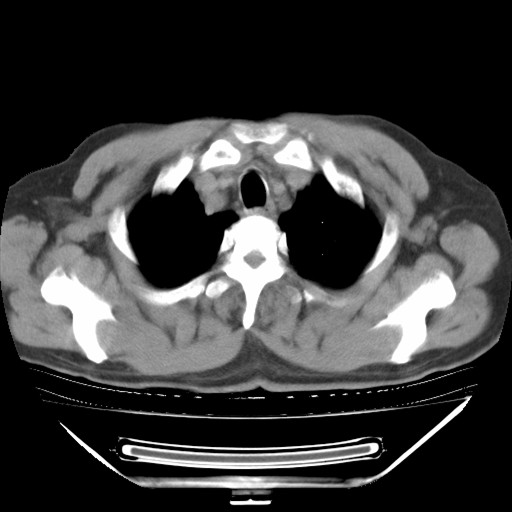

以下是引用hhcckk在2009-5-29 10:34:00的发言:[br]左下肺片絮状边缘模糊影,考虑感染,建议治疗后复查[br]